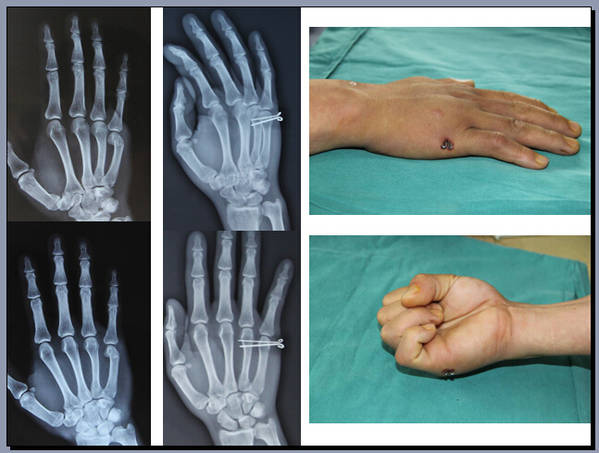

手外科会议带去一个讨论题目